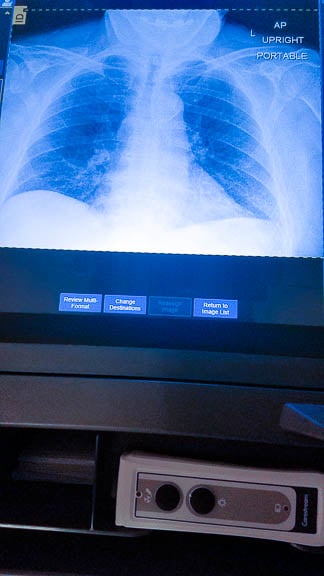

New Digital Portable Xray Machines

The Diagnostic Radiology Technologists put to work four new Carestream Digital Portable Xray units during the surge of Covid-19 patients over the last four months. Deb Pellegrino, Diagnostic Lead on the University Campus called the new units a “lifesaver.” The units were used to x-ray nearly every Covid-19 and trauma patient as well as the rest of the portable exams. The digital capabilities allowed the images to be viewed while still on the floor and uploaded directly to the PACs system. Thus, saving time, allowing for immediate repeated imaging when necessary while providing better patient care and less donning and doffing full PPE. The older analog units required techs to leave the floors to process the images and the physical aspect of carrying the CR plates.

In a normal month the portable units are utilized for 2,000 plus xrays. During the Covid-19 surge of 3,000 a month the portable units were a necessity for access to patients, prevent the spread of infection, and assist with staff safety. The use of the digital units amplified the benefits tremendously by improving image quality and cutting the exam turn-a-around time in half.